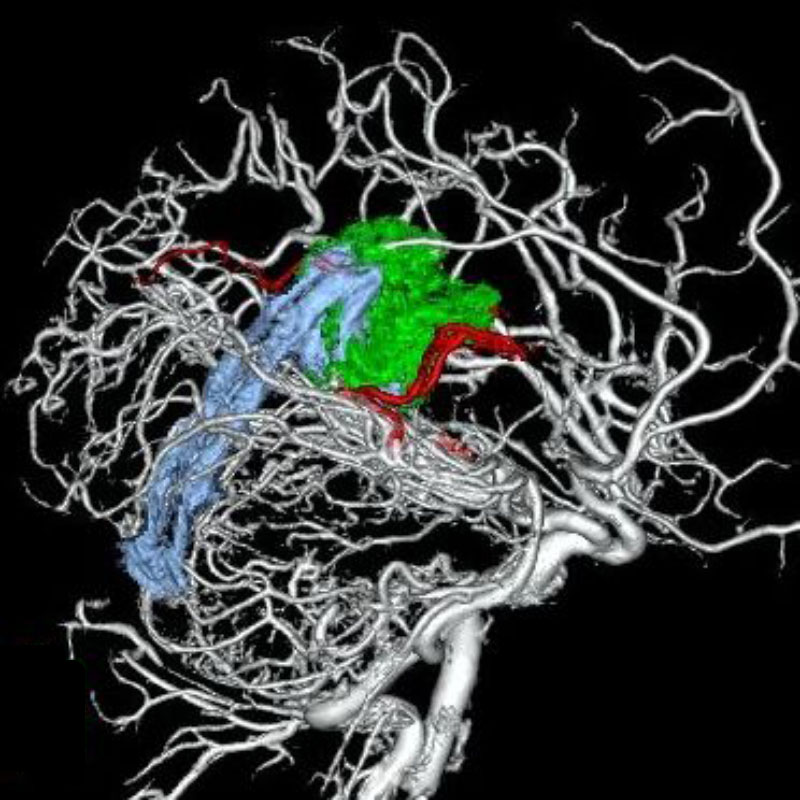

脳動静脈奇形

摘出術

南田/野本/古谷/元永

血管塞栓術

芝野/古谷